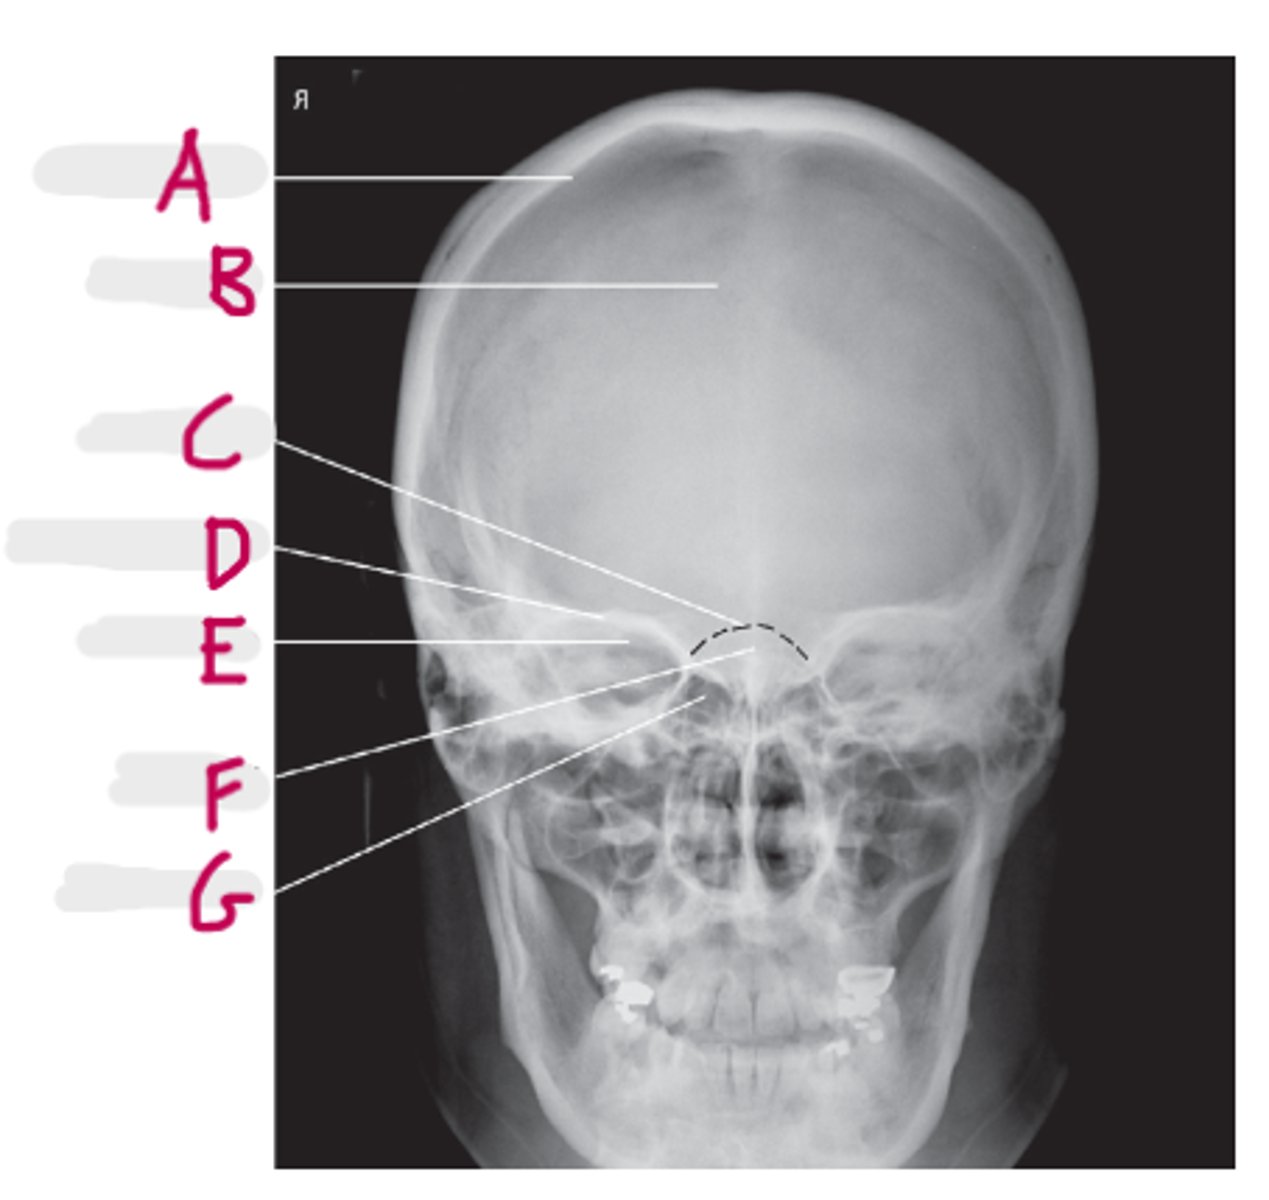

PA axial (Caldwell Method)

What projection is this?

CR exits the nasion & 15 degree caudal angle

What is the CR for PA axial (Caldwell Method)?

OML perpendicular to IR

What line should be perpendicular to the IR for a PA axial (Caldwell Method)?

Interpupillary line (IPL)

What line is parallel to the IR for a PA axial (Caldwell Method)?

Frontal and Ethmoid

What sinuses are clearly demonstrated on the PA axial (Caldwell Method)?

Lower 1/3 of orbits

Where are the petrous ridges located in a PA axial (Caldwell Method) radiograph?

Frontal Sinuses

A

Ethmoid Sinuses

B

Maxillary Sinus

C

Petrous ridge

D

Mastoid air cells

E